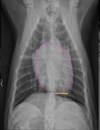

What are the signs of generalized cardiomegaly?

combination of signs involving both left and right cardiac chambers -right and left heart enlargement

46

What is shown in these images?

generalized cardiomegaly